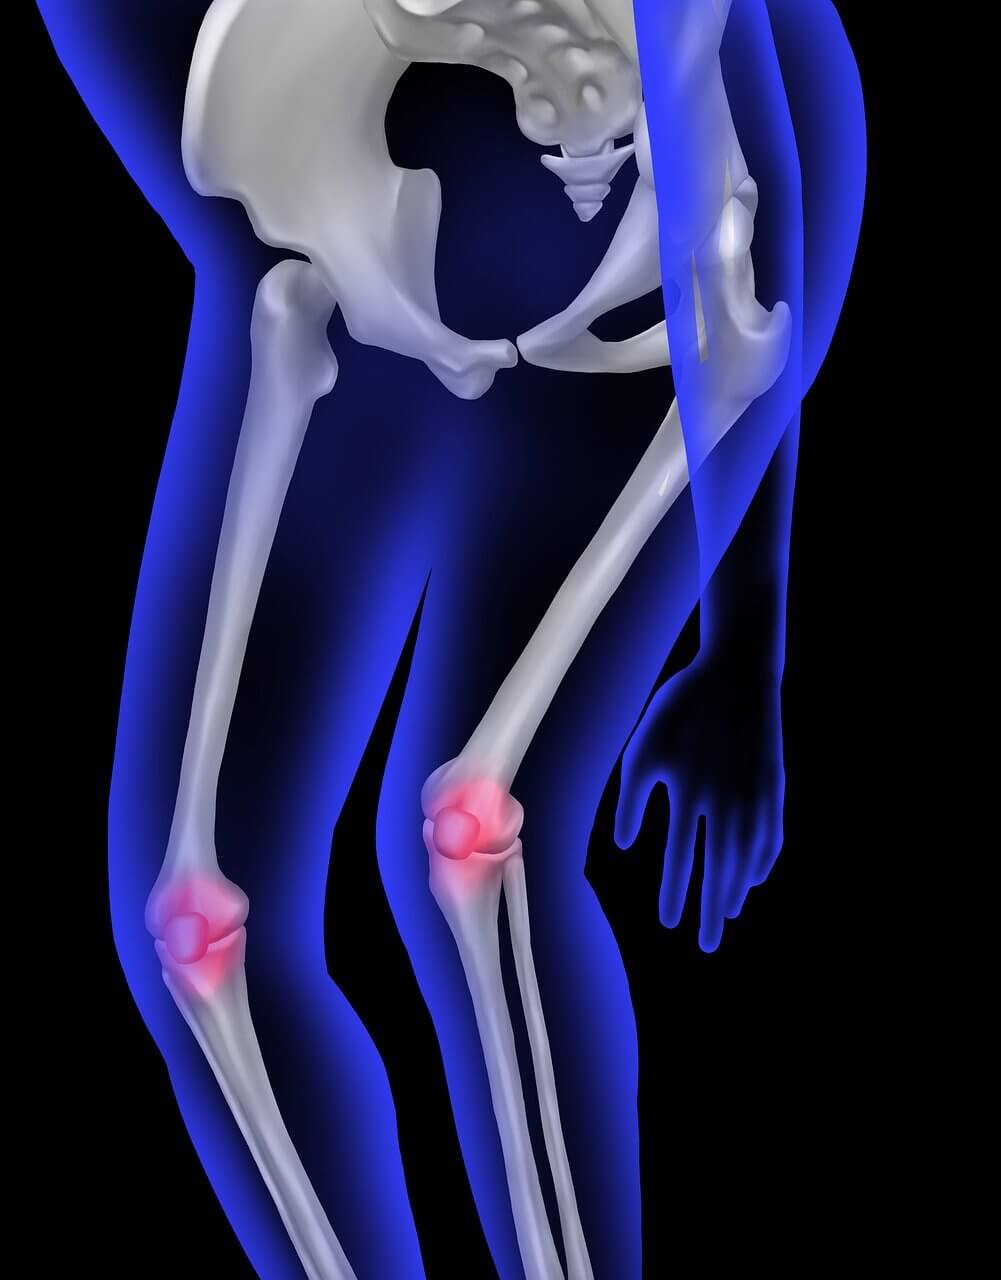

전방십자인대는 무릎 안쪽 깊숙이 위치하며 대퇴골과 경골을 연결해 무릎이 앞뒤로 흔들리지 않도록 잡아주는 역할을 합니다. 쉽게 말해, 무릎의 중심을 지탱하는 ‘핵심 줄’과도 같습니다. 전방십자인대 파열이 일어나면 무릎이 헐거워지고, 체중을 지탱하기 어려워집니다.

3. 전방십자인대 파열의 주요 증상

- 무릎에서 ‘뚝’ 소리가 나거나 끊어지는 느낌

- 부상 직후 심한 통증과 빠른 부기 발생

- 걷거나 방향을 바꿀 때 무릎이 휘청거림

이러한 증상이 있다면 전방십자인대 파열 가능성이 높으므로 즉시 움직임을 멈추고 의료기관을 찾아야 합니다.